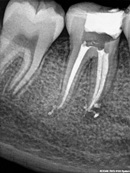

Root Canal Cases